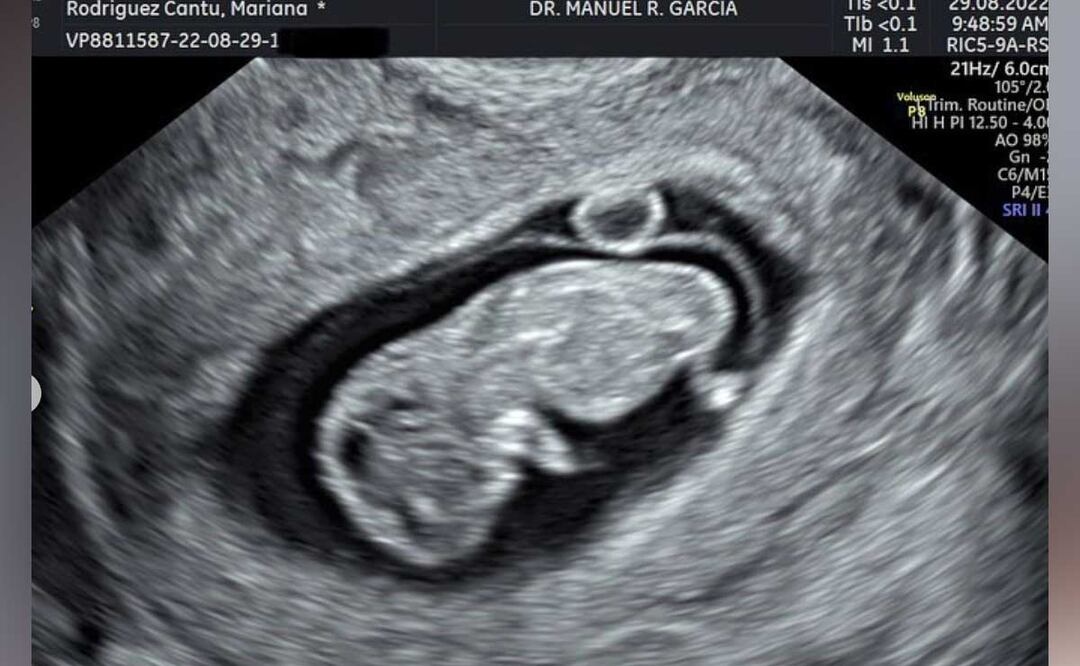

En las primeras horas de este lunes 29 de agosto, la pareja más controversial de redes sociales compartió una selfie con la ecografía.

La pareja compartió a sus seguidores que estaban contentos por la llegada del bebé, de quien aún no se conoce el sexo.

“Baby on the way! Estamos felices de compartirles que pronto seremos 3”, así inicio su publicación Mariana Rodríguez, quien a pocos minutos de ser compartida en su cuenta, acúmulo miles de me gusta y más de seis mil comentarios.